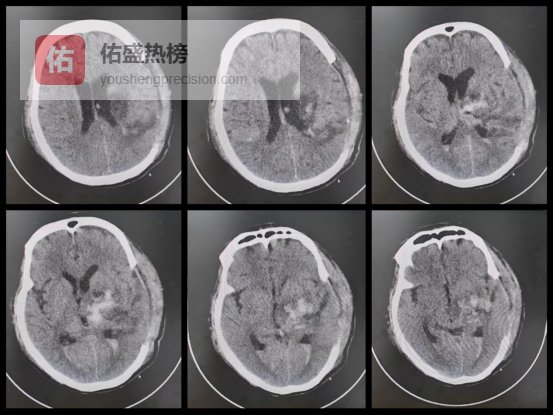

急诊CT显示,阿文大脑左侧基底节区出现大面积高密度血肿,脑组织受压移位、中线偏移,脑疝风险极高,生命危在旦夕。基底节区是大脑运动神经传导核心,此处出血极易导致肢体偏瘫、失语,死亡率和致残率极高。

(术前 CT 影像:高密度血肿清晰可见,压迫着脑组织)

术后复查CT显示:颅内血肿已被完全清除,受压的脑组织得到有效解除,中线恢复正常,颅内压力也回归平稳,阿文的生命体征逐渐平稳,成功从死亡线上被拉了回来。

(术后 CT 影像:血肿已彻底清除,手术区域干净)